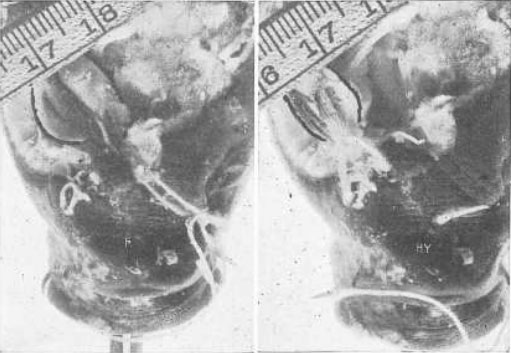

Рис. 18. Демонстрация на глазном яблоке кролика того, что косые мышцы удлиняют зрительную ось при миопии

R, состояние покоя. Глазное яблоко имеет нормальную длину и находится в состоянии эмметропии – то есть полностью настроено на зрение вдаль. Му, миопия. Натяжение косых мышц было усилено путем их перемещения, и ретиноскоп показал, что возникла миопия. Легко заметить, что глазное яблоко стало длиннее. Было невозможно избежать какого-либо движения головы между съемкой этих двух кадров, на которых изображены результаты манипуляции с нитями. Но линейка показывает, что фокус камеры не был сильно изменен такими перемещениями.